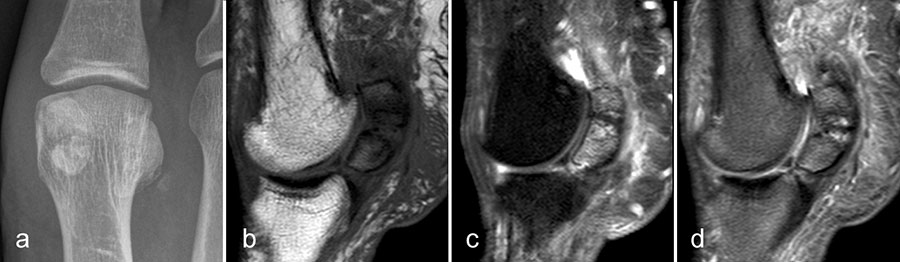

Wenn Stressreaktionen- und frakturen Folge einer offensichtlichen Überlastung sind, ist die Diagnose in aller Regel klinisch und anamnestisch zu stellen. Die MRT dient eher der Unterscheidung zwischen reiner Stressreaktion und bereits eingetretener Fraktur (Abb. 1).

Bei inadäquater Besserung unter Entlastung kann der Ausschluß einer chronischen Stressreaktion oder einer sich entwickelnden Pseudarthrose ein Grund für eine MRT Untersuchung sein (Abb. 2).

Diese Art der Stressfraktur, bei der ein gesunder Knochen einer unphysiologischen und vor allem ungewohnten Belastung ausgesetzt wird, wird auch als Ermüdungsfraktur bezeichnet.

Für den klinischen Kollegen besonders diagnostisch herausfordernd sind Ermüdungsfrakturen dann, wenn der Grund für die Überlastung vom Patienten nicht selbst erkannt wird. Neue Schuhe, Einlagen oder auch eine veränderte Belastung durch Schmerzen in einem anderen Gelenk sind häufige Gründe, die durch eine exakte Anamnese aufgedeckt werden können. Auch Stressfrakturen an ungewöhnlichen Lokalisationen können klinisch diagnostische Probleme bereiten (Abb. 3).

Auch die Insuffizienzfraktur, also die Fraktur eines zu schwachen Knochens unter physiologischer Belastung, wird oft erst durch die MRT erkannt. Sie betrifft häufig ältere Patienten mit Osteoporose, oder Patienten, die länger entlasten mussten und eine Inaktivitätsosteopenie aufweisen. Insuffizienzfrakturen kommen jedoch auch vor, ohne dass die Ursache für die Insuffizienz bekannt ist (Abb. 4). In diesen Fällen werden sie als idiopathisch bezeichnet. Meist sind Insuffizienzfrakturen bei Diagnosestellung rein subchondral oder trabekulär lokalisert. Der rechtzeitige Nachweis dieser Frakturen ist von besonderer Bedeutung um eine weitere Belastung zu vermeiden und dem Risiko des Einbruchs mit möglicher Entwicklung einer Osteonekrose vorzubeugen.